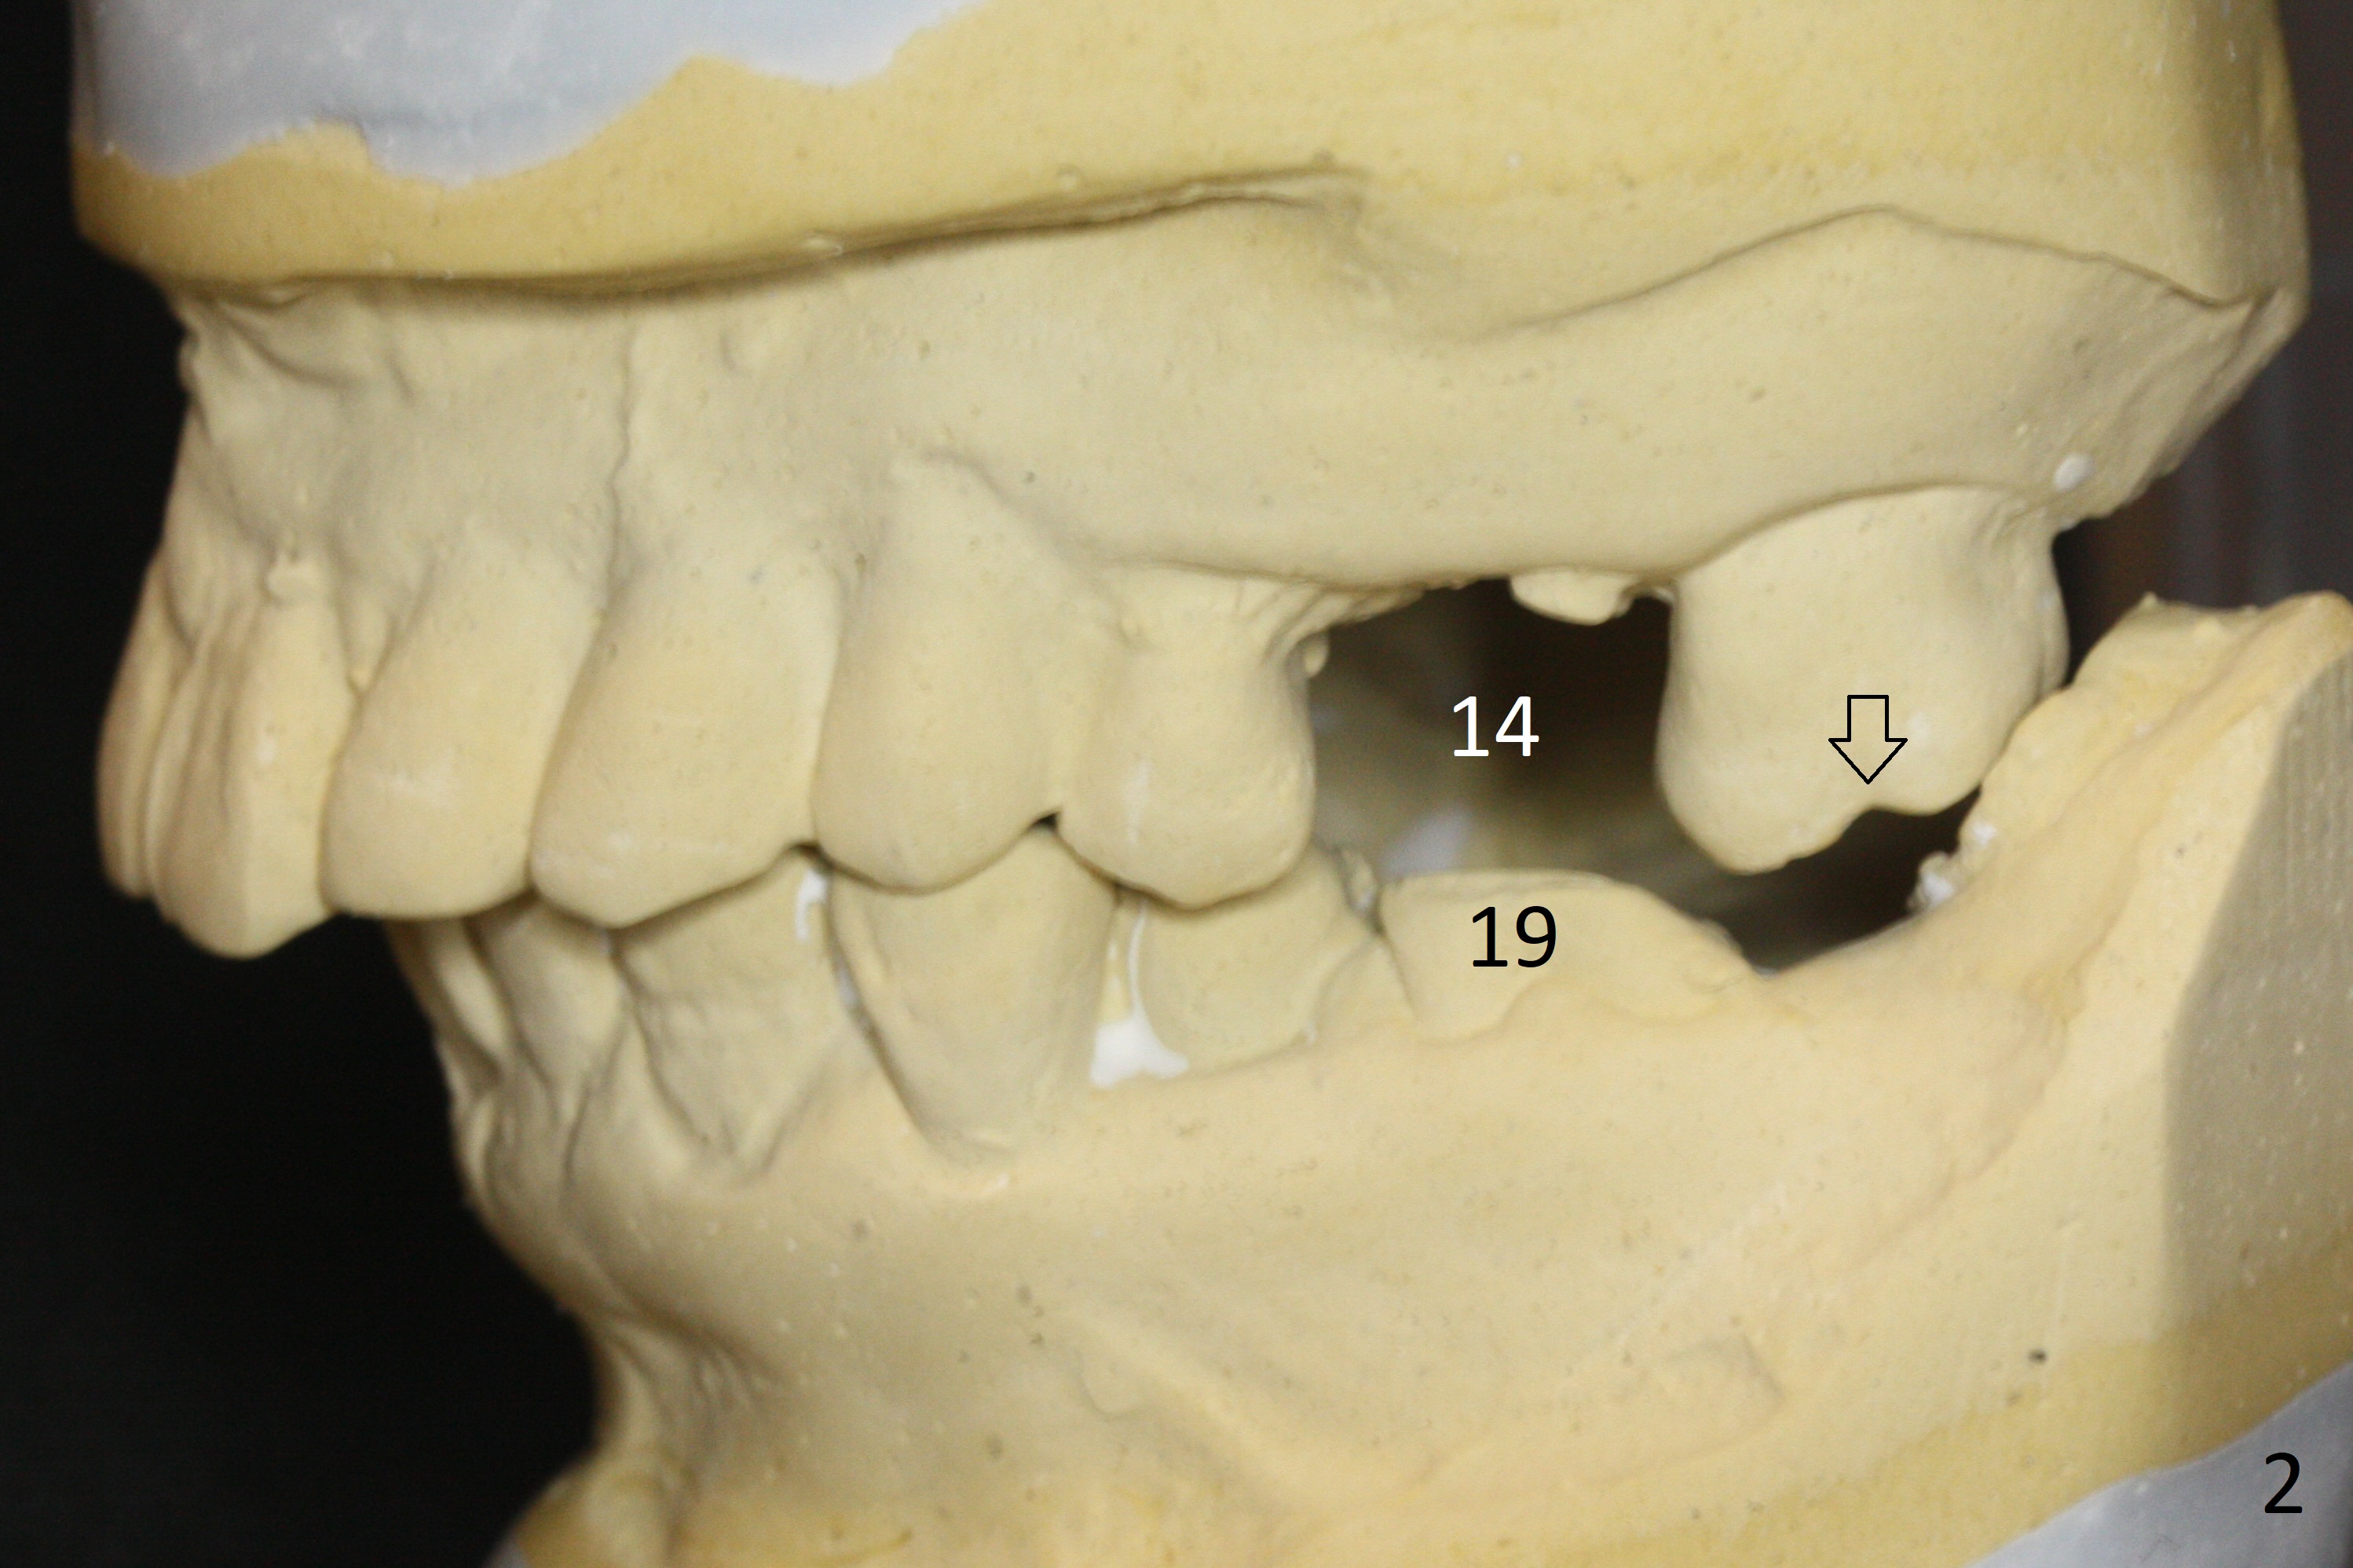

A 54-year-old man is 5 years post liver cancer surgery. After his platelet count returns normal, he wants to take care of his teeth. Most of his molars (#14, 19, 30,31) need extraction and implant placement (Fig.1-4). Although the 2nd premolars on the right are missing (Fig.1,3,4), it seems appropriate to establish 2 molar occlusion on the right (Fig.5,7,8) and 1 on the left (Fig.6,7 (because of #15 supraeruption (Fig.2 arrow))) . Since the residual roots in the lower right quadrant are irritating, implant placement will be done first (Fig.11, Clindamycin), followed by #2,3 (Fig.10) and 14(Fig.12 IBS) and 19 (Fig.12). Use IS drills and 4 and 5 mm stoppers to start osteotomy at #30 and 31, respectively.